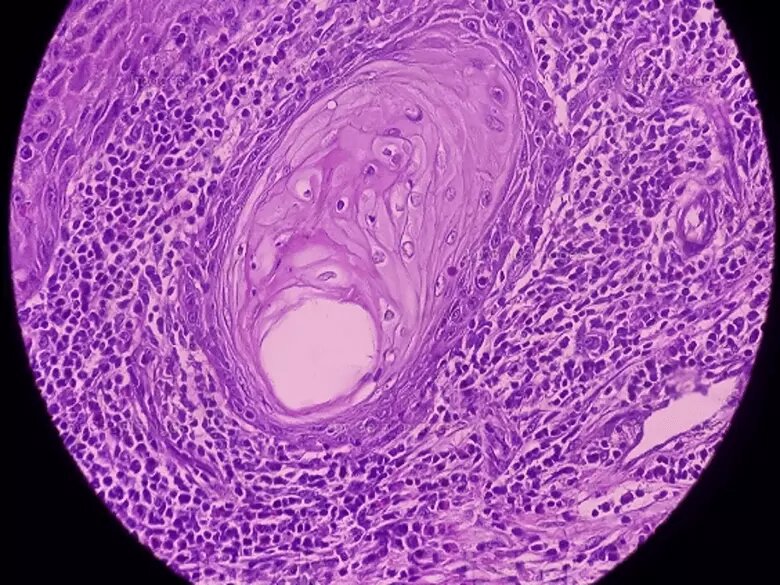

Биопсия шейки матки позволяет точно установить природу различных новообразований, проще говоря, выявить присутствие раковых (злокачественных) клеток.